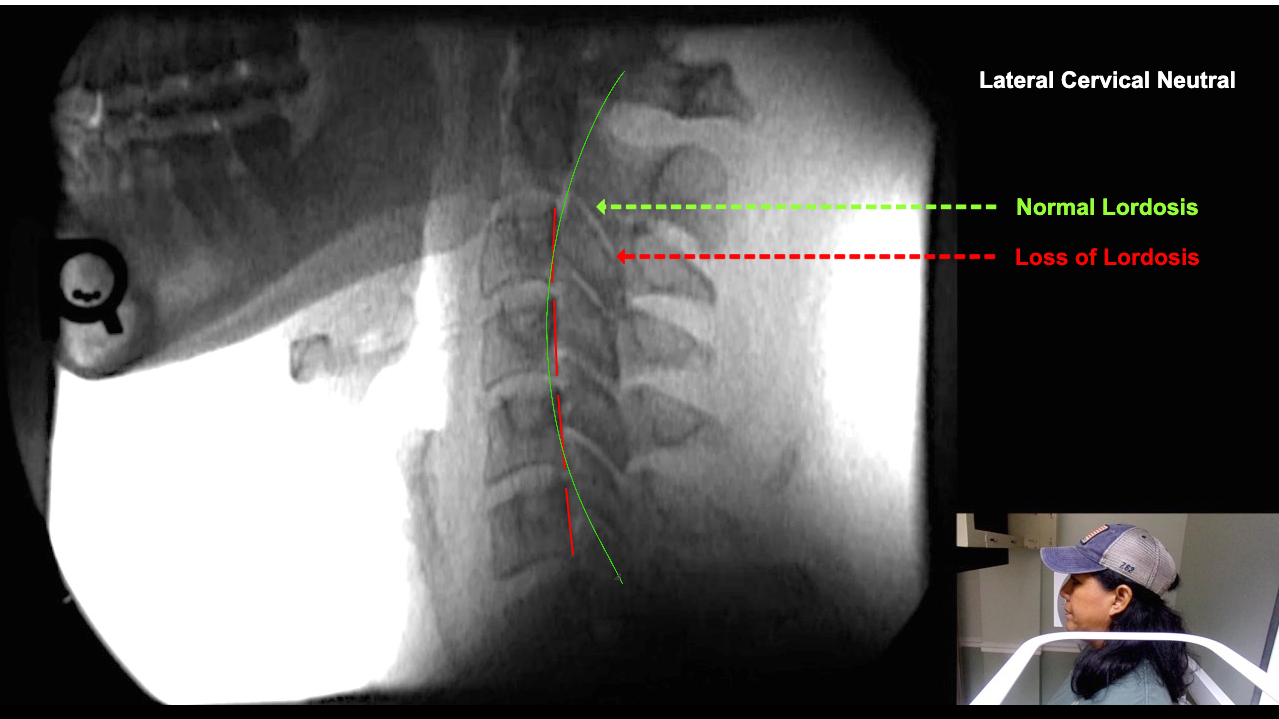

Image Name Image Type Image

Image 2